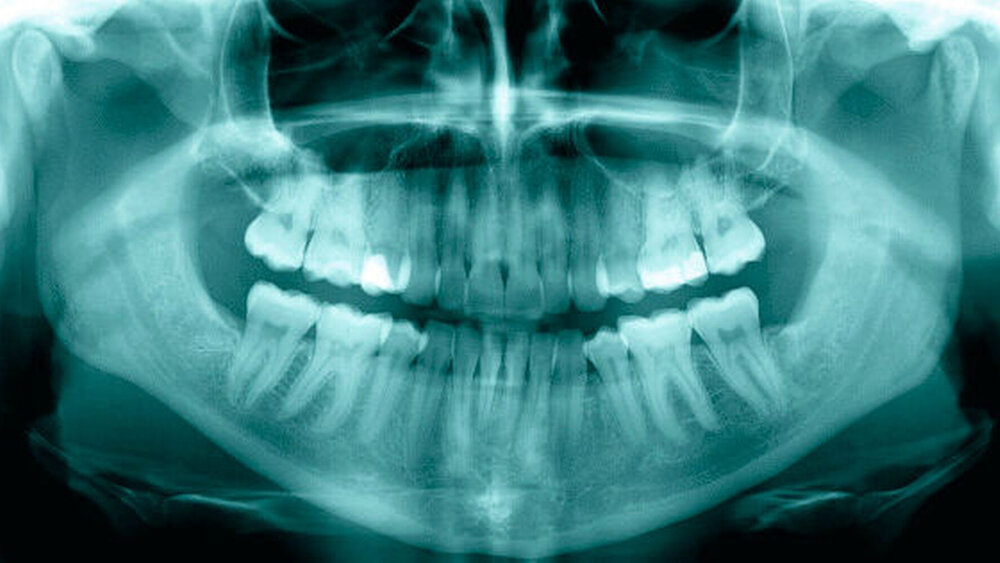

„Hirntumore durch Röntgen der Zähne“ – auf diese plakative Formel brachte die „Welt“ in ihrer Online-Ausgabe vom 12. April vergangenen Jahres die Ergebnisse einer an der Yale-Universität durchgeführten Studie [Claus et al., 2012]. Untersucht worden war das Meningeom-Risiko durch dentale Röntgendiagnostik, wobei teilweise eine Verfünffachung des Risikos postuliert wurde. Nun kann man sich der medialen Aufmerksamkeit sicher sein, wenn es um die „Krebsgefahr“ geht, selbst wenn es sich in diesem Fall um einen gutartigen Tumor handelt. Es verwundert deshalb nicht, wenn in der Folge auch sonst eher wissenschaftsfern orientierte Regionalblätter in zum Teil halbseitigen Artikeln über diese vermeintlich neue Gefahr aus der Zahnarztpraxis berichteten. Besorgte Anfragen von verunsicherten Patienten waren die Folge.

Vor diesem Hintergrund erscheint es natürlich überraschend, dass die geringen effektiven Dosen, die bei der dentalen Röntgendiagnostik appliziert werden (in der Größenordnung der ohnehin auf jeden einwirkenden natürlichen täglichen Strahlungsbelastung), einen statistisch nachweisbaren Effekt auf das Tumorrisiko haben sollen. Zweifel an der Validität der Studie wurden deshalb schnell laut und auch in den Zahnärzt-lichen Mitteilungen geäußert.

Als herausstechende Ergebnisse beschreiben die Autoren im Abstract eine um den Faktor zwei gegenüber der Kontrollgruppe erhöhte Wahrscheinlichkeit, dass Patienten von mindestens einer Bissflügelaufnahme berichten, sowie ein um den Faktor fünf erhöhtes Risiko für das Auftreten eines Meningeoms bei Patienten, bei denen in einem Alter von unter zehn Jahren nach ihrer Erinnerung mindestens eine Panoramaaufnahme gemacht wurde. Etwas weniger prominent, im Diskussionsteil, findet sich der Hinweis, dass sich im Fall von Statusaufnahmen keine statistisch signifikante Erhöhung des Risikos zeigte.